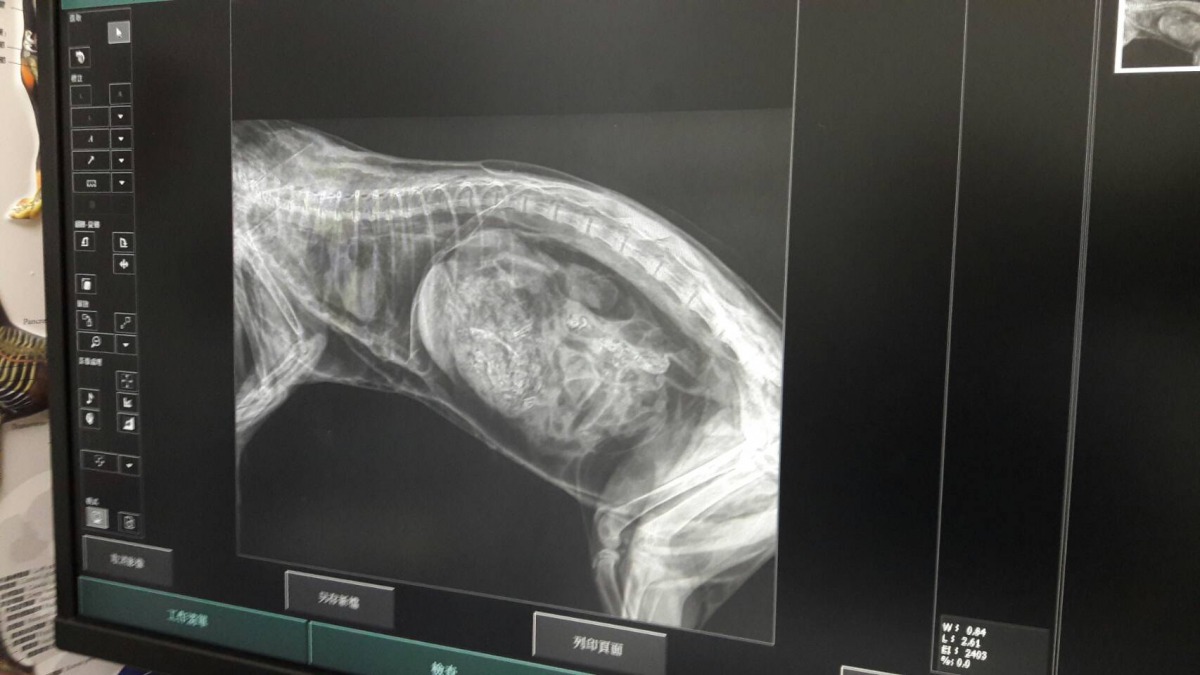

在苗栗後龍的這起路殺,主角是一隻幼年母石虎,地點十分靠近市區,兩側皆是農田,也是該路段的第一起路殺事件。苗栗縣農業處保育科指出,經獸醫師檢查,發現這隻石虎才剛換門牙,年約4、5個月大,應該還沒脫離母親的照顧,胃裡有食物,根據X光影像,保育科人員推測這隻小石虎在死前吃的是白腹秧雞,可能才剛吃飽沒多久便遭遇路殺。

而在南投中寮鄉的這起路殺,對象是一隻有生產經驗的成年母石虎。根據當地養雞戶的通報,有一隻老鼠和一隻石虎雙雙死在路旁,特生中心指出,從乳頭可判斷這是一隻有生產哺育經驗的母石虎,而經獸醫師拍攝X光,確認這隻石虎的頭部有遭撞擊的痕跡,胃中則有滿滿的食物,推測這隻石虎雖然已經吃飽,還是被死在路上的鬼鼠所吸引,形成「二次路殺」。